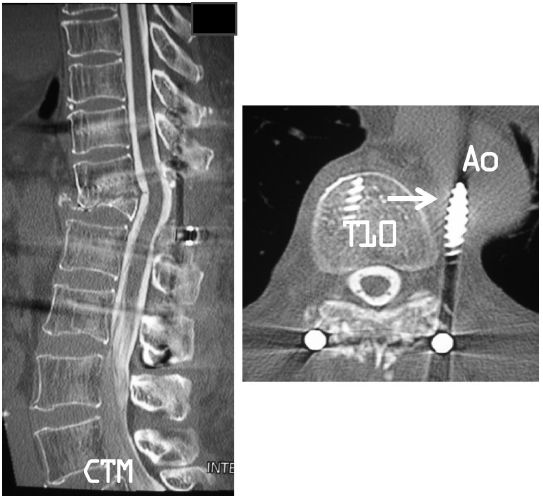

患者拔除引流管后佩带支具开始康复活动。术后4周常规CT脊髓造影示左侧T10椎弓根螺钉偏出,与胸主动脉后内侧接触,未见周围血肿(图3)。但行血管造影发现错位的T10椎弓根螺钉已穿透胸主动脉壁(图4)。

图3 CT脊髓造影显示骨折处脊髓充分减压,左侧T10椎弓根螺钉错位,与胸主动脉后内侧接触(白色箭头)

图4 CT血管造影显示,错位的T10椎弓根螺钉尖端穿透胸主动脉壁(白色箭头)